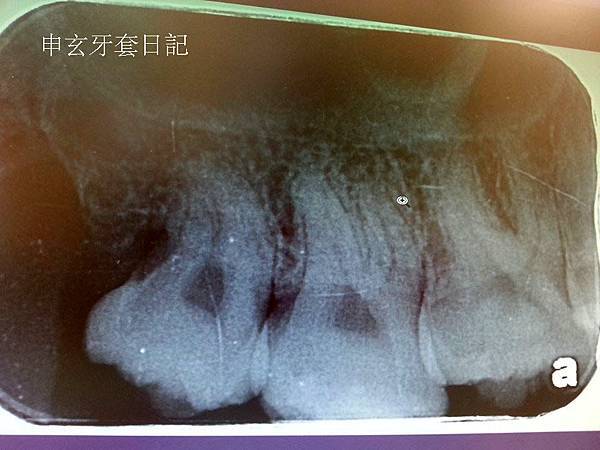

我下面的左右智齒都是最靠北的"水平智齒",水平智齒要開刀才能拔出來~

第二次拔牙是今年6月多,因為智齒那的牙齦好像發炎,所以就跑去拔了,

因為也是水平智齒,一樣拔了一個多小時,拔完一週後去拆線,